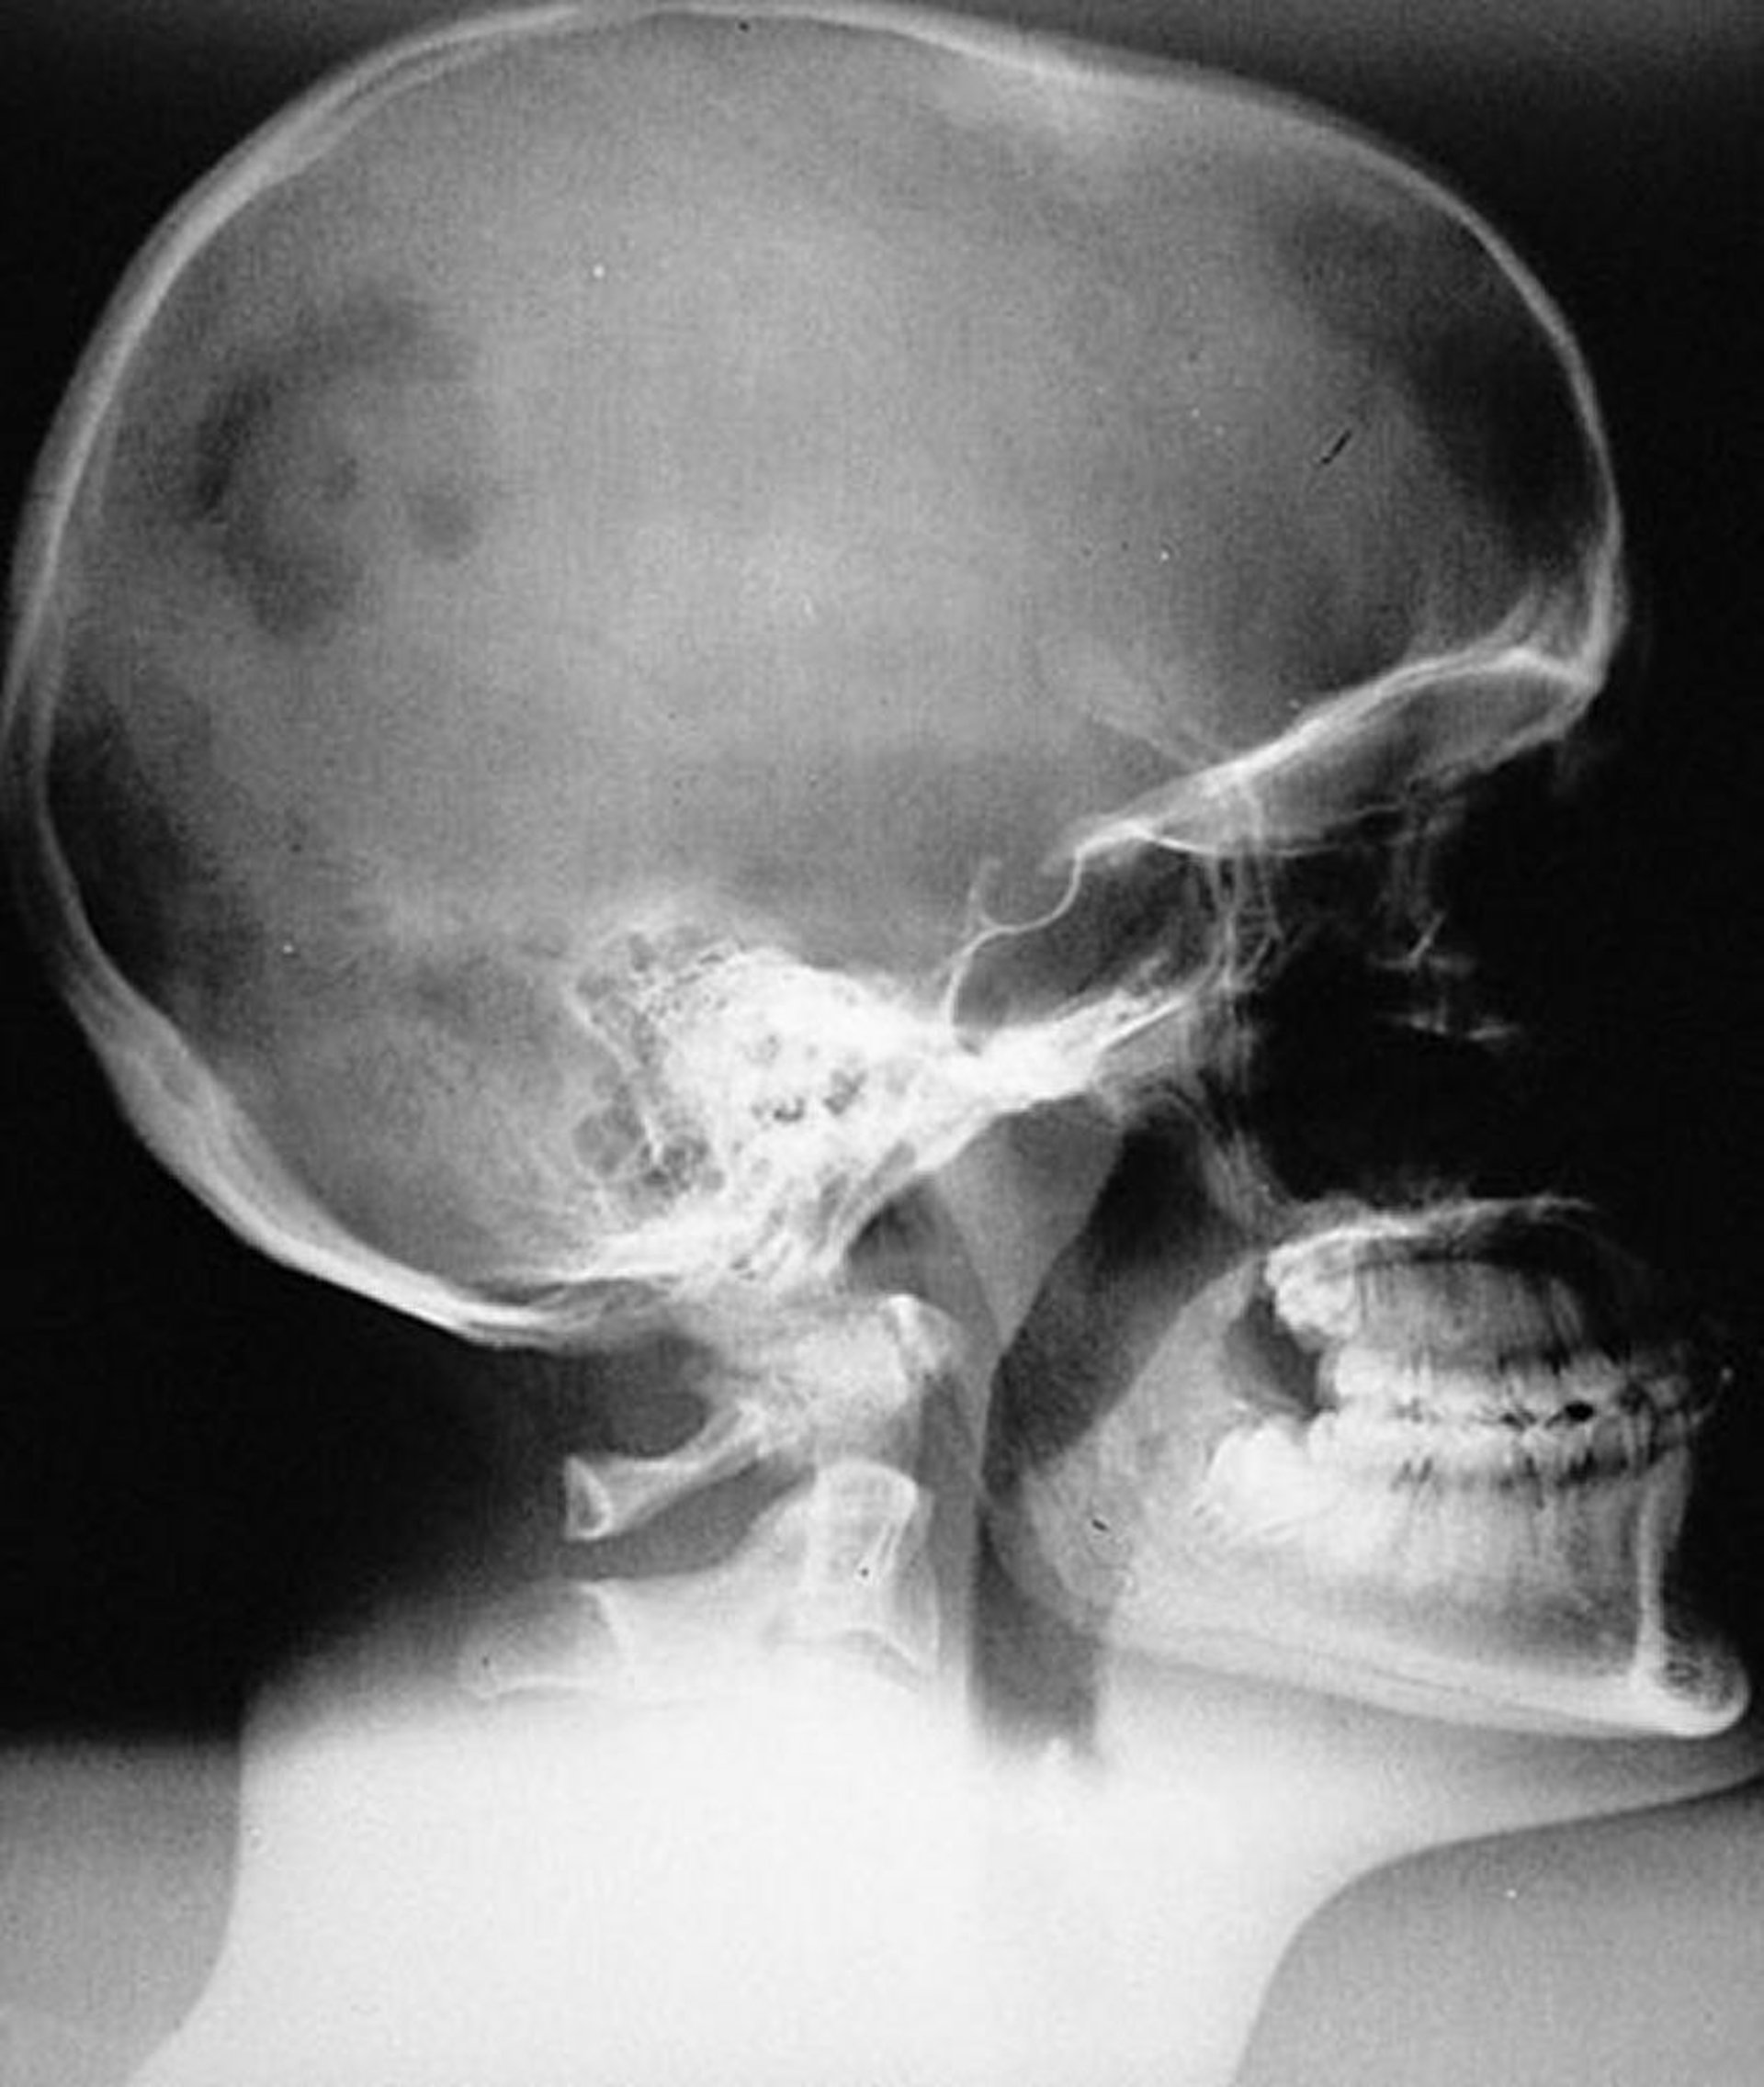

Bệnh mô bào Langerhans (u hạt do tăng bạch cầu ái toan) ở hộp sọ

Hình ảnh chụp X-quang của tổn thương LCH đơn ổ điển hình (u hạt do tăng bạch cầu ái toan) ở hộp sọ. Các tổn thương bị rìa sắc nhưng không được vát.

Được sự cho phép của nhà xuất bản. Theo Swearingen B, Schaefer P, Primavera J, Klibanski A. Trong Atlas of Clinical Endocrinology: Neuroendocrinology and Pituitary Disease. Biên tập bởi S Korenman (biên tập loạt bài) và ME Molitch. Philadelphia, Current Medicine, 2000.